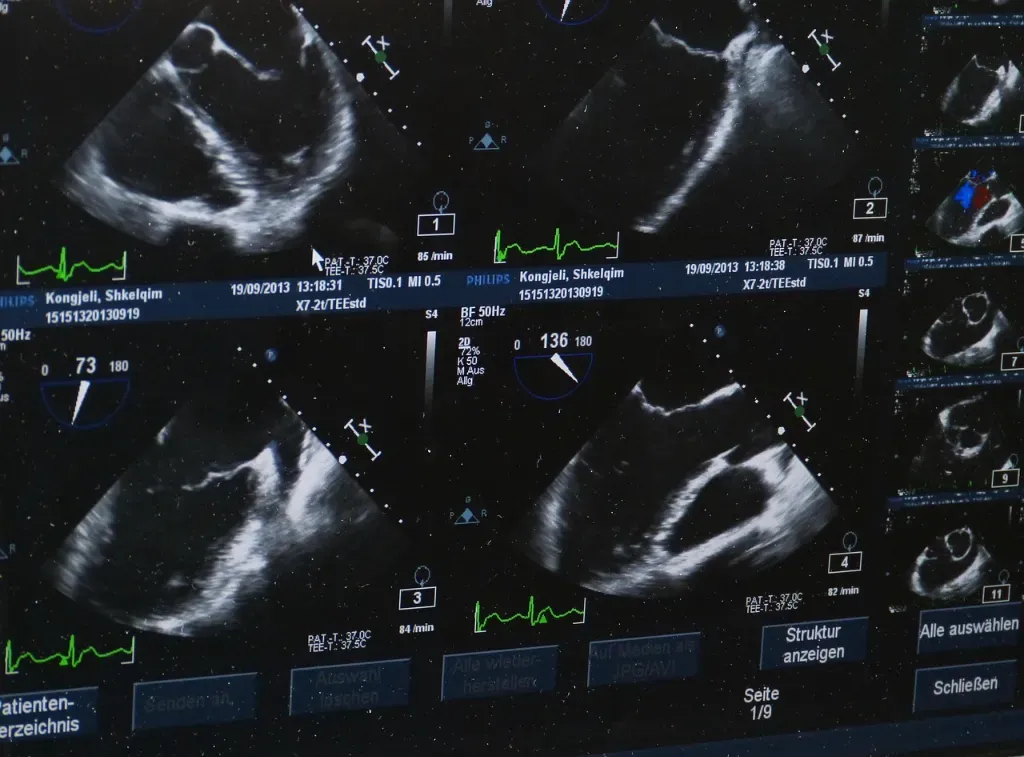

Mimo kompaktowych rozmiarów, nowoczesne przenośne aparaty USG oferują wysoką jakość obrazowania porównywalną z tradycyjnymi stacjonarnymi urządzeniami. Dzięki zaawansowanej technologii cyfrowej obrazy są wyraźne i szczegółowe, co pozwala na precyzyjną ocenę stanu zdrowia pacjenta.